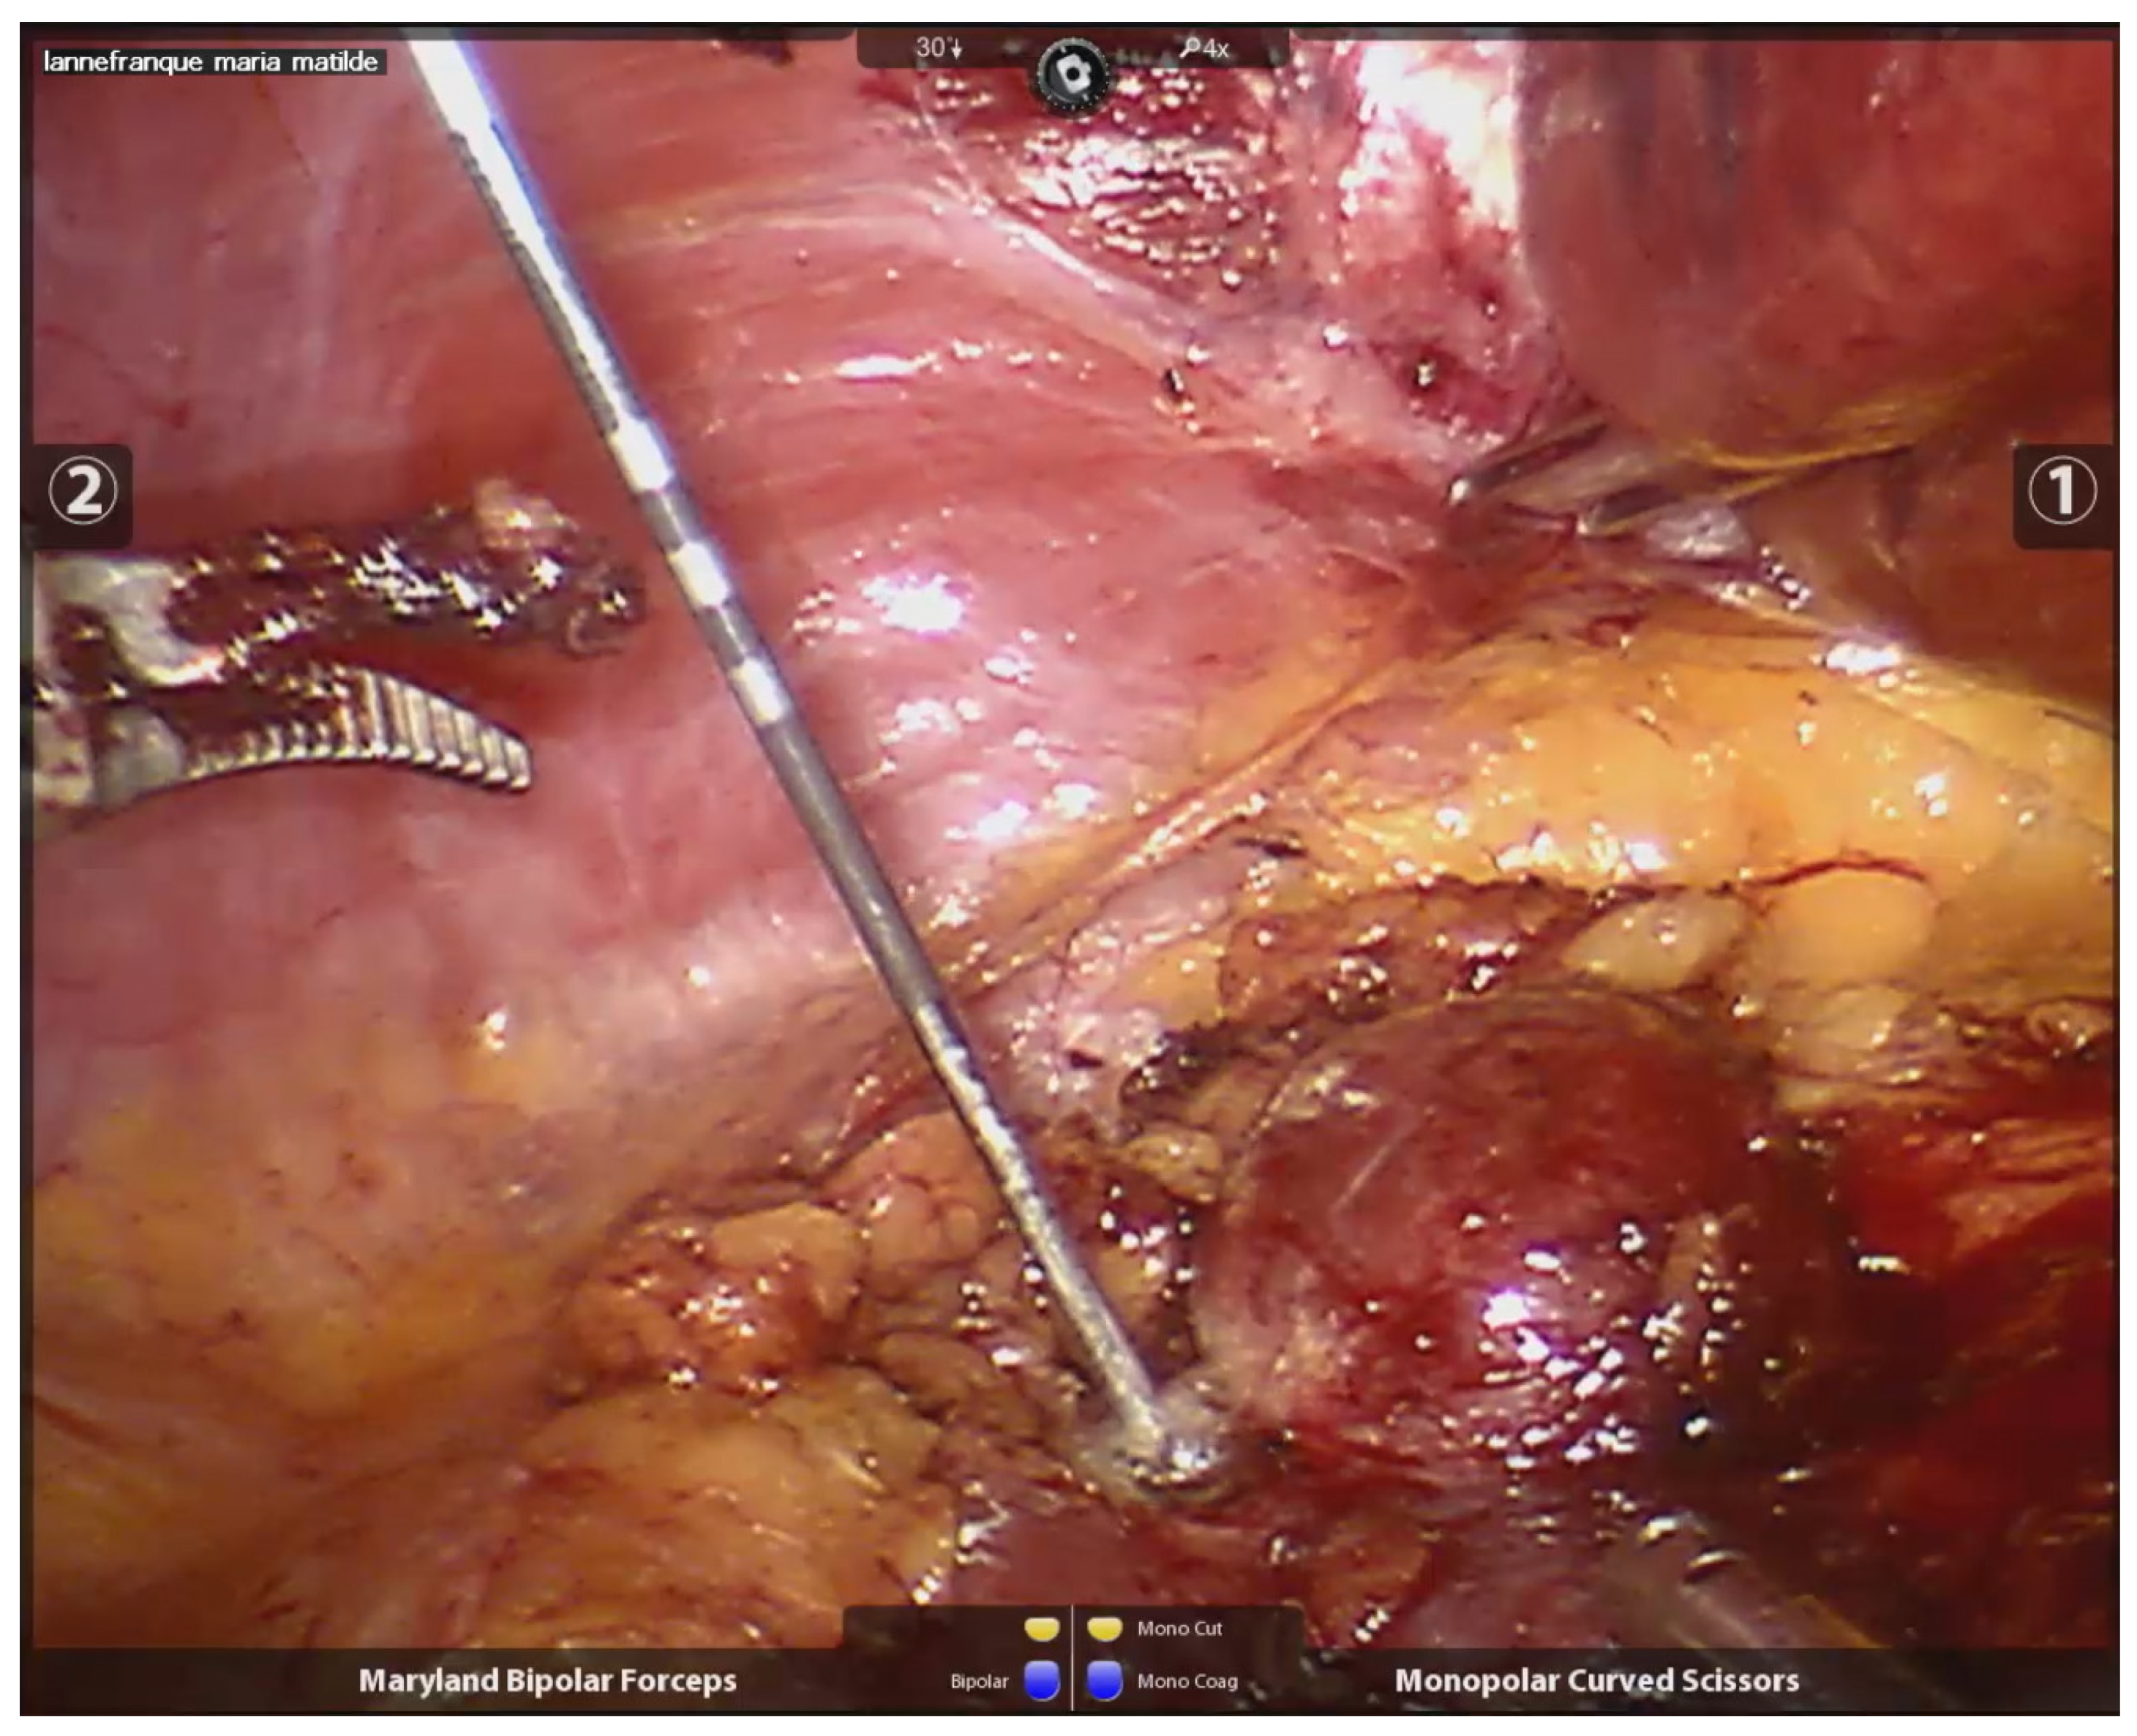

2.2. Procedure and Technique